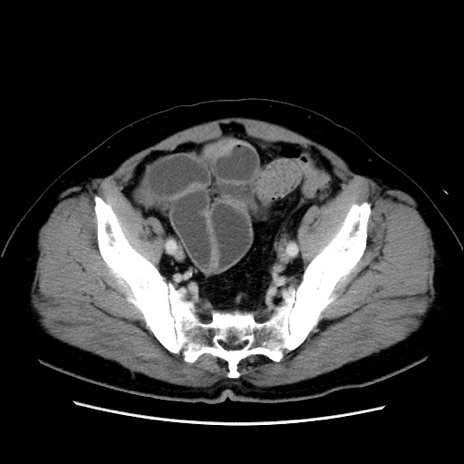

症例16(横断像)

【症例】 70歳代男性

【主訴】 腹痛、嘔吐

【現病歴】 約1ヶ月前より間欠的に腹痛と嘔吐あり、当院消化器内科を受診したところCTで多発する肝臓のLDAを指摘され、精査中であった。以降は消化器症状は安定していたが、2日前より嘔気と腹痛があり、同日より排便・排ガスが消失した。改善認めず、 本日、救急外来を受診した。

【既往歴】 大腸ポリープ切除後。

【身体所見】意識清明・会話良好、BT 36.3℃、BP 127/80mmHg、 P 80bpm、腹部:膨満あり、平坦・軟、上腹部正中および下腹部正中に圧痛あり、反跳痛なし、筋性防御なし。

【データ】WBC 7200、CRP 0.77